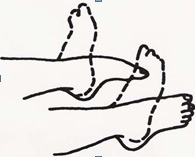

به پشت دراز بکشید یا بنشینید، خم شوید و مچ پا را به سرعت صاف کنید. این حرکت را 20 بار تکرار کنید. این تمرین برای جلوگیری از تشکیل لختههای خون مفید است.